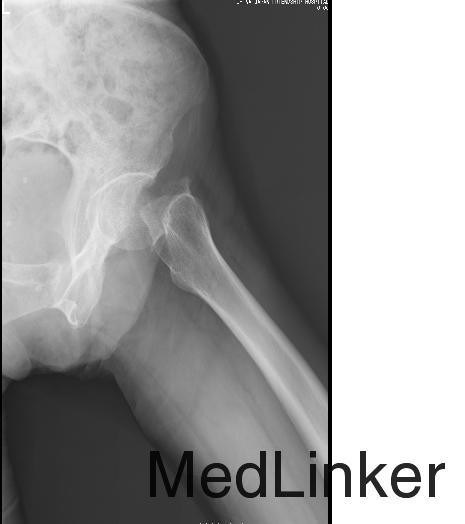

患者,女,62岁,主因“摔伤后左髋部疼痛伴活动受限1天”入院。患者昨日于家中活动时不慎摔伤,左髋部着地,遂感左髋部剧痛,不能自行站起,被家人送至我院急诊科就诊,行X线检查后诊断为"左股骨颈骨折",予左下肢皮牵引等处理。现患者为行进一步治疗,以“股骨颈骨折”收入我科。

查体:平车推入病房。左下肢屈曲、外旋畸形,较右下肢短缩约2cm。左髋部无明显肿胀,腹股沟中点及左髋外侧压痛(+),左下肢轴向叩击痛(+)。左髋关节活动受限。 辅助检查:左髋关节正侧位X线:左侧股骨颈骨折,完全移位。

诊断:左侧股骨颈骨折(Garden Ⅳ型) 治疗:行左侧全髋关节置换术